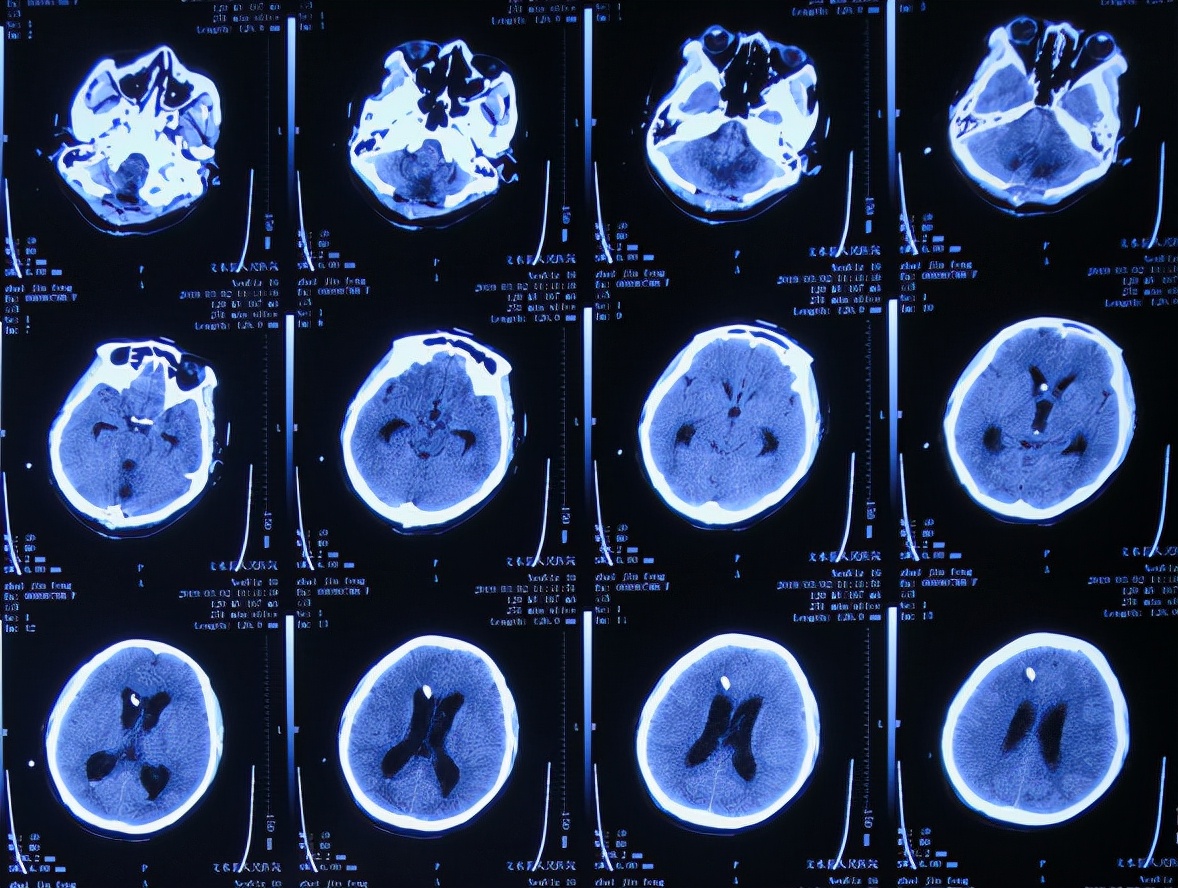

脑出血脑室外引流术后次日即2019年2月19日,复查头颅CT示出血未见明显减少( 图-3 )。

图-3: 2019年2月19日头颅CT

但脑出血脑室外引流术3天即2019年2月21日,出现尿崩症状,查头颅CT示脑室仍有出血( 图-4 );给予口服弥凝2天后症状好转,查血电解质示低钠、低钾,但给予积极纠正但效果仍不理想。

图-4: 2019年2月21日头颅CT

脑出血脑室外引流术7天即2019年2月25日,查头颅CT示出血明显好转( 图-5 )。

图-5: 2019年2月25日头颅CT